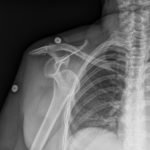

Bedside ultrasound with the transducer placed on the posterior right shoulder revealed an anterior dislocation of the right humerus. This is evident by displacement of the humeral head further away from the posteriorly placed ultrasound transducer, and appears deep to the glenoid cavity. In a posterior shoulder dislocation, the humeral head would appear closer to the transducer (and the near field of the ultrasound image) than the glenoid. Note that a hypoechoic, heterogeneous fluid collection is within the joint space, compatible with a hematoma. A right shoulder X-ray confirmed the anterior dislocation with no evidence of fracture. Under direct ultrasound guidance the glenohumeral joint space was injected with 10 mL of 2% lidocaine as an intraarticular anesthetic block. The right shoulder was reduced using continual traction. Post-reduction ultrasound demonstrated a successful shoulder reduction, depicted by the humeral head being relocated to its anatomical location, adjacent to the glenoid cavity, as noted on the ultrasound image. A hematoma remains present within the joint space. Successful shoulder reduction was further confirmed by X-ray. The patient’s arm was placed in a sling and she was discharged home with orthopedics follow-up.